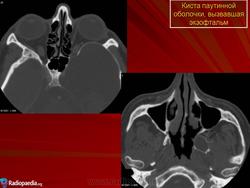

До 4 % кист локализуется глубоко в орбите. Это так называемая котомковидная дермоидная киста орбиты, описанная Kronlein в конце XIX в. Образование состоит из трех частей: головка кисты — ампулообразное расширение — находится за пределами тарзоорбитальной фасции в глубине орбиты, хвост кисты — в височной ямке, а перешеек — в области лобно-скулового шва. Для такой локализации характерно длительное (иногда в течение 20—30 лет) постепенное увеличение экзофтальма. Опухоль, смещая глаз в сторону, ограничивает функции экстраокулярных мышц, появляется диплопия. Увеличение экзофтальма до 7— 14 мм сопровождается постоянными распирающими болями в орбите. Нарушение зрения может быть обусловлено изменением рефракции вследствие как деформации глаза, так и развивающейся первичной атрофии зрительного нерва. Котомковидную кисту обычно диагностируют после 15 лет. Длительно существующая киста может распространяться в полость черепа. Диагноз подтверждают с помощью рентгенографии орбиты (выявляют истончение и углубление костного края орбиты в зоне расположения кисты). Наиболее информативна компьютерная томография, при которой хорошо визуализируются не только измененные костные стенки, но и сама киста с капсулой.